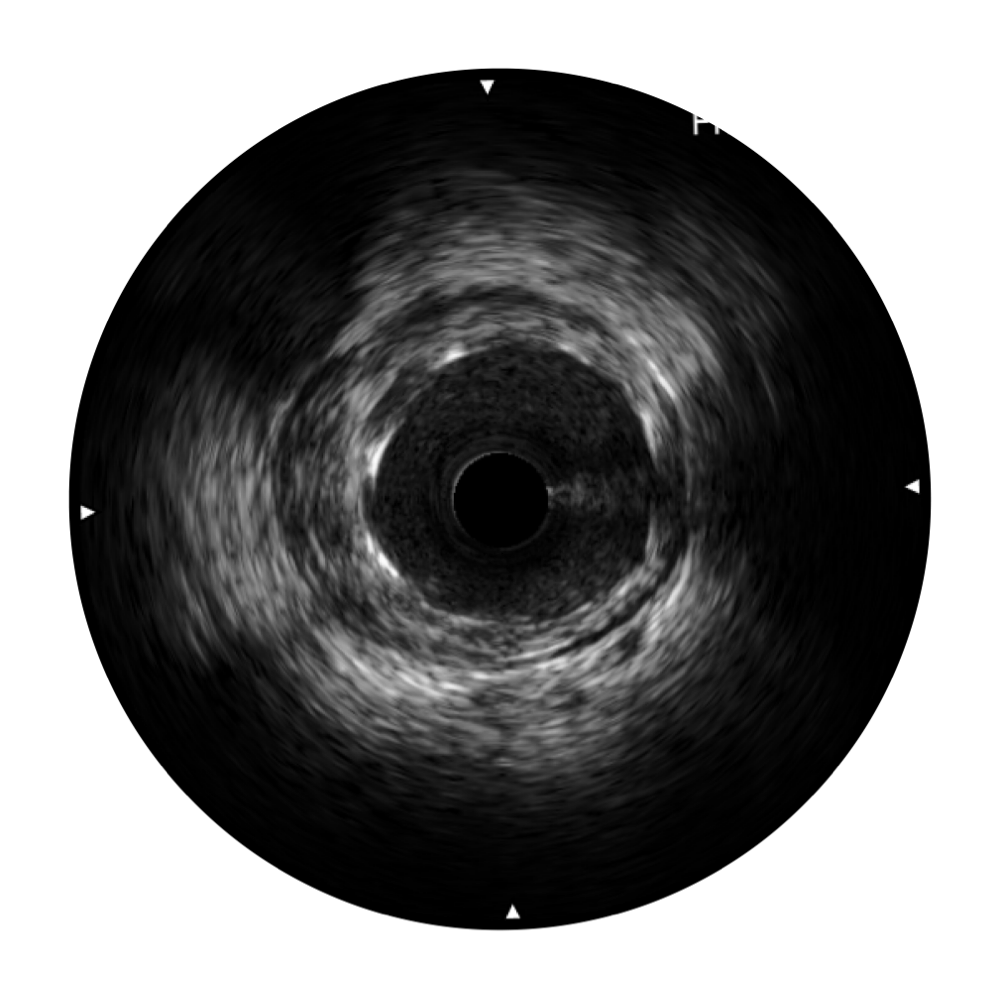

血管内超声(IVUS) 通过对病变程度、性质和累及范围的精确判断,可帮助选择治疗策略和方法,指导介入治疗过程,能够降低主要不良心血管事件,改善预后,在复杂病变介入治疗中用于指导支架置入的优势更为明显。血管内超声(IVUS)已成为精准心血管介入治疗的“金标准”。

亚星官网始终关注未满足的临床需求:超宽频成像技术同时提供高清分辨力和充足穿透深度,适应不同血管结构的治疗引导;智慧赋能,简化操作,降低临床应用难度和缩短学习曲线。

亚星官网超宽频成像技术覆盖20-80MHz1或20-90MHz2频率范围, 提供优异的分辨力同时也保证充足的穿透深度

对比传统IVUS导管成像,亚星官网宽频IVUS图像的近场支架梁显影更细腻,远场中膜外血管仍清晰可辨,兼顾远中近,兼顾分辨力与穿透深度